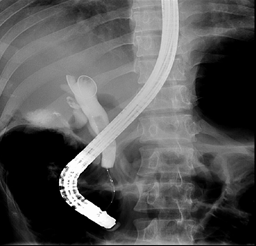

Al tercer día fue remitido a hospital terciario. Con fines diagnósticos y terapéuticos, se procedió a realizar colangiopancreatografia endoscópica retrógrada (Fig 5). Durante el proceder, al paso de la sonda, se demostró papila duodenal normal. Seguidamente se canalizó el colédoco. El colangiograma evidenció un gran defecto lineal de llenado en el colédoco y múltiples pequeños defectos de llenado en el conducto hepático derecho, asociados a no visualización del conducto hepático izquierdo. Se procedió a realizar esfinterotomía biliar y extracción de los cálculos de las vías biliares mediante barrido con balón, el conducto hepático derecho lucía con reducción de su diámetro por estenosis fibrótica que, aunque permitió el paso de la sonda, no fue posible la colocación de stent. No obstante, se logró colocar stent en el colédoco. Se complementó tratamiento con antibioticoterapia, piperacilina y tazobactam por vía intravenosa. Posterior a la colangiopancreatografia endoscópica retrógrada, se planteó el diagnóstico de colangitis piógena recurrente.